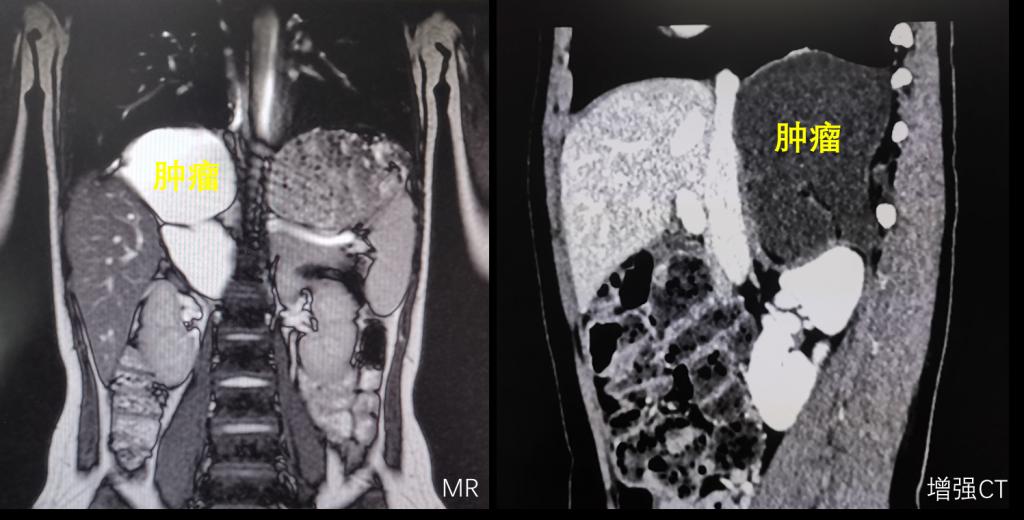

渭南某地10岁小姑娘因为间断性的腹痛到医院检查,意外发现腹腔内有一直径超过10cm巨大肿瘤。慕名来到我院小儿外科就诊。常规的超声检、磁共振和CT检查,都提示腹膜后有一个巨大肿瘤,而且这个肿瘤位置非常特殊,它长在肝脏、下腔静脉和腹主动脉等重要脏器和血管的后方,膈肌的下方,如果按照常规的手术思路,经腹手术,暴露困难,视野不佳,手术的难度和风险极大,而且只能是开放手术,创伤也会大大增加。

怎么样能够降低手术风险,也能够达到家属期望的微创治疗?经过多次讨论,鉴于肿瘤巨大及特殊位置,李鹏教授团队突破常规思维,提出经胸腔镜下切除腹膜后肿瘤的方案,利用胸腔空间大,切开膈肌后,暴露充分,手术的风险和难度反而大大降低,而且李鹏教授团队有丰富的胸腔镜操作的经验和技术,经过反复研究影像学资料和讨论,最终制定了胸腔镜下腹膜后肿瘤切除的方案及备选方案。